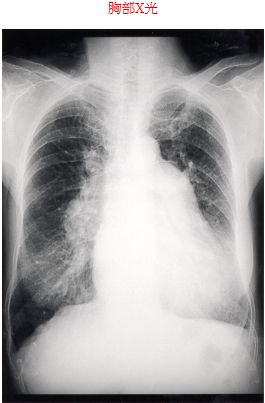

8. 75歲女性病人因有兩週之運動性呼吸困難,於九十年五月二十三日住院, 病人自訴自成年後經常有感冒並因此有運動性心悸, 40歲時因感冒求診,首度有醫師告知心臟病。這個病人近年感覺生活尚屬良佳,但每週幾乎都有感冒及氣喘情形。70歲時有心臟衰竭住院之記錄,近2週的呼吸困難、伴有食慾不振、噁心、嘔吐及腹瀉情事,才住院診療。理學檢查:體型瘦小老女人、外表病弱、血壓130/70mmHg、心跳76次/ 分、呼吸18次/分、體溫37℃、頸動脈微張、肺部無異常,但心臟檢查有fixed splitting of S2及強度P2,在左胸緣第3肋間區有第四度 systolic ejection murmur及右下胸骨緣有變動性第3度diastolic rumblingmurmur之異常,又有輕度腳水腫但無杵指,其他都是正常。其心電圖及胸部X光圖。本病人之正確診斷為: (A) 僧帽瓣狹窄 (B) 僧帽瓣閉鎖不全 (C) 主動脈瓣狹窄 (D) 心室中隔缺損 (E) 心房中隔缺損